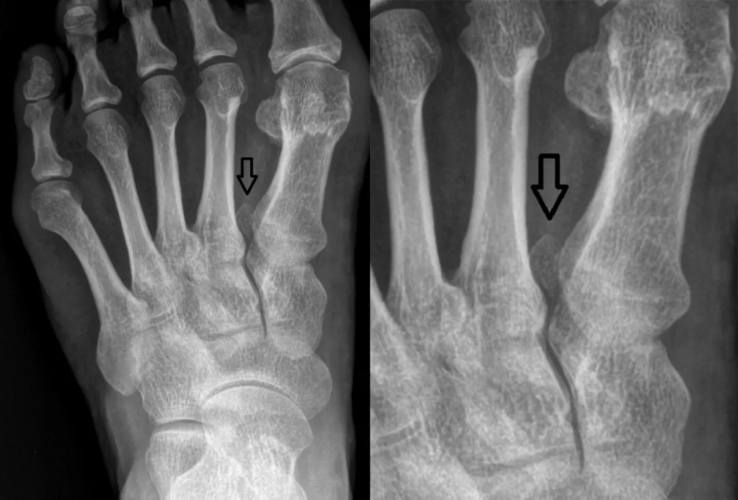

足踝撕脱性骨折与籽骨分不清楚?背下这张图再也不会漏

籽骨骨折